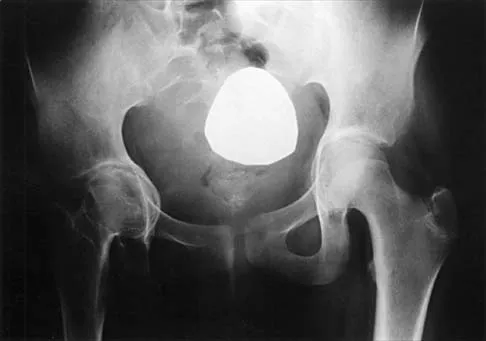

Figure 44 shows the radiograph of an 11-year-old girl who has hip pain. Further diagnostic workup should include

Explanation

The patient has severe acetabular protrusio, a condition that is frequently associated with Marfan syndrome. An echocardiogram is necessary to rule out the most serious consequence of this syndrome, aortic root widening, which can lead to aortic valve dysfunction or fatal aortic rupture. An electromyogram may be indicated for Charcot-Marie-Tooth disease, which is associated with acetabular dysplasia, but not protrusio. The renal ultrasound, the MRI scan, and the biopsy would be of no value in this patient. Protrusio can also be seen in patients with osteogenesis imperfecta and juvenile rheumatoid arthritis. Steel HH: Protrusio acetabuli: Its occurrence in the completely expressed Marfan syndrome and its musculoskeletal component and a procedure to arrest the course of protrusion in the growing pelvis. J Pediatr Orthop 1996;16:704-718.